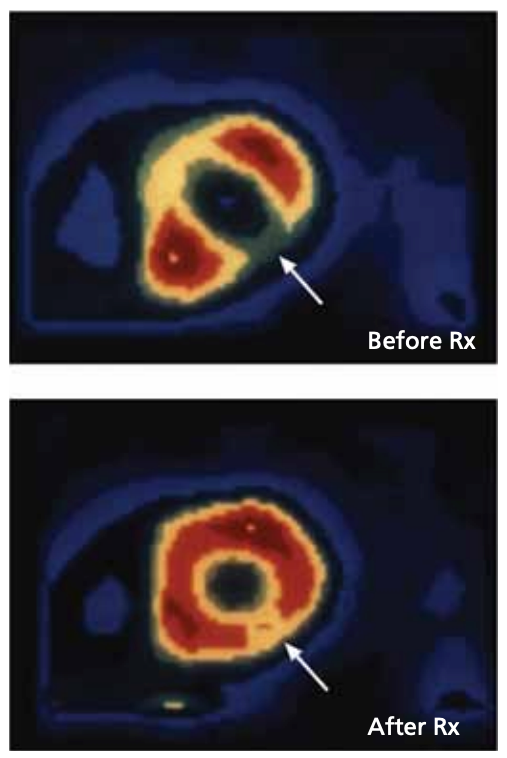

- In the Esselstyn Heart Disease Program conducted by Dr Caldwell Esselstyn, patients with severe CAD saw a halt in disease progression, restoration of blood flow through the heart muscle (myocardial perfusion) and significant angiographic reversal of atherosclerosis. Symptoms diminished and often disappeared within 12 weeks. Cardiac events ceased in 97.8% of patients.

Above: PET scan shows normal blood flow restored to heart muscle after 3 weeks of lifestyle intervention.

Credit: Dr Caldwell B. Esselstyn